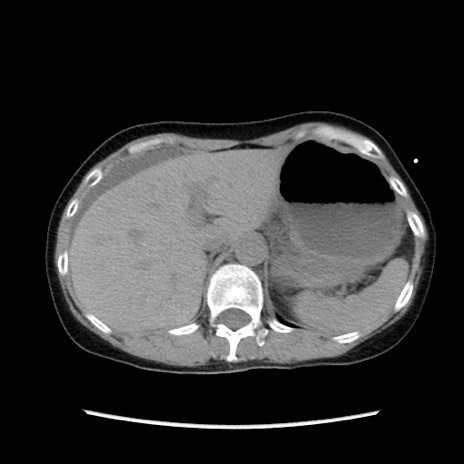

矢状断像

【症例】40歳代 女性

【主訴】上腹部痛、嘔気・嘔吐

【現病歴】約9時間前頃から急に上腹部痛、嘔気、嘔吐が出現。改善しないため救急要請。

【既往歴】子宮頚癌(広汎子宮全摘術、放射線療法)、腸閉塞

【身体所見】腹部:平坦、軟、腸雑音亢進、上腹部を中心に腹部全体に圧痛あり。

【データ】WBC 8400、CRP 0.03